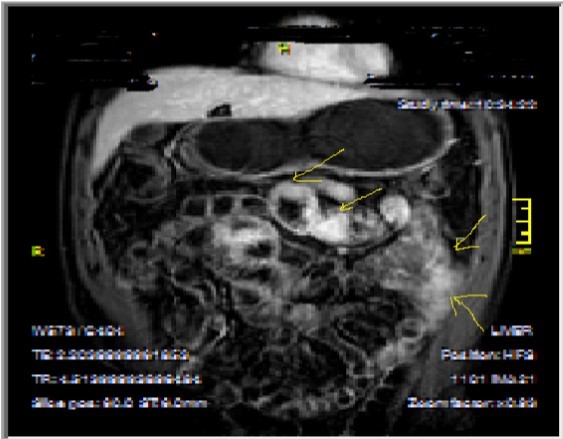

Figure 3a-3b-3c.Diffuse mucosal involvement and extreme luminal narrowing in the terminal ileum due to Crohn’s disease on T2W coronal sequence after OCA administration, stricture and string sign near ileo-ceccal valve in Figure 3b.